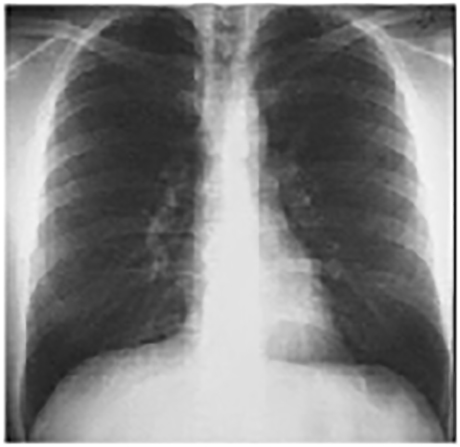

Your choice: Normal PA and Lat

These chest X rays are normal. The pa view demonstrates no abnormalities of the bone structures, lung fields, or cardiac silhouette. The right and left heart borders are normal as are the great vessels superior to the cardiac silhouette. Note the cardiothoracic ratio is also normal, that is, it is less than 50%.